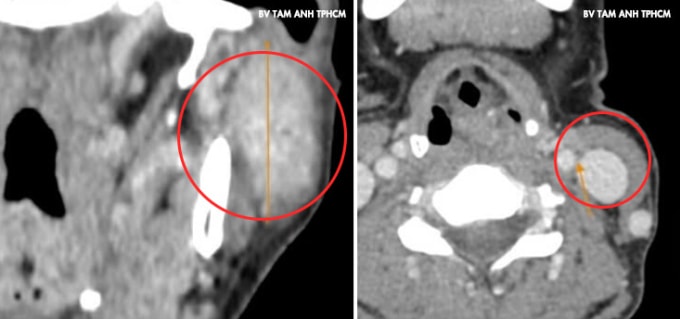

U xuất hiện ở góc hàm mang tai trái của chị Dương một năm trước, nhỏ và không đau, không liệt mặt, khác với đặc điểm chung của loại u này là thường phát triển rất nhanh gây đau và liệt dây thần kinh mặt. Gần đây, u sưng hơn khiến mặt mất cân đối, chị đến Phòng khám Đa khoa Tâm Anh Quận 7 kiểm tra. Kết quả chụp CT và siêu âm ghi nhận khối u dài hơn 4 cm chiếm gần hết mô tuyến mang tai trái, phát triển vào trong xâm lấn dây thần kinh 7 và tĩnh mạch sau hàm. Cạnh trước khối u có hạch gần 1 cm và hai hạch hơn 1 cm vùng cổ. Kết quả sinh thiết chọc hút tế bào kim nhỏ là u tuyến mang tai hóa bọc, chưa xác định ung thư.

GS.TS.BS Trần Phan Chung Thủy, Giám đốc Trung tâm Tai Mũi Họng, Bệnh viện Đa khoa Tâm Anh TP HCM, cho biết bệnh nhân có u tuyến mang tai ở cả thùy nông và thùy sâu, khả năng rất cao là u ác tính, đã di căn hạch cổ. Tuy nhiên, để xác định chính xác cần phẫu thuật lấy u và giải phẫu bệnh.